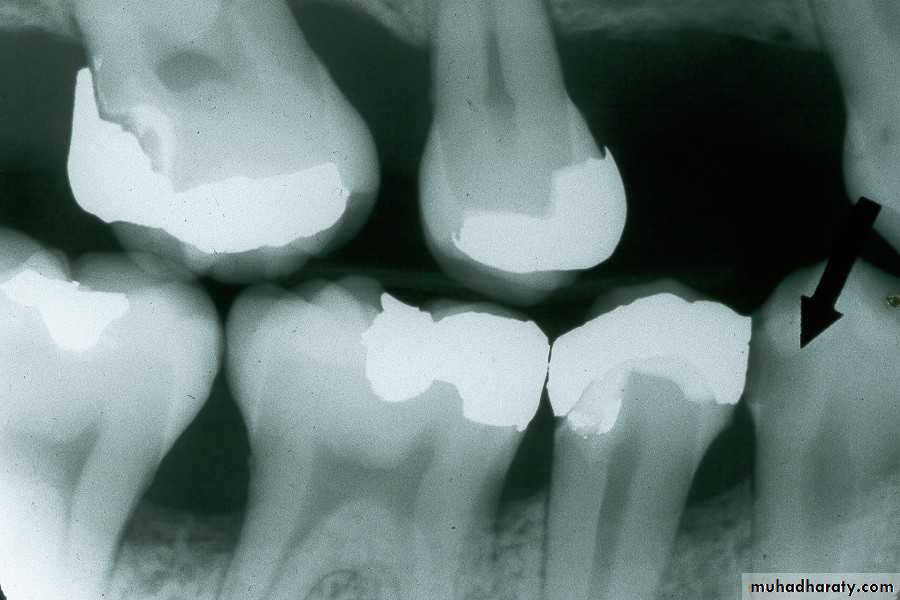

just below the cemento-enamel junction (CEJ) on the mandibular second premolar.Found around the margins of existing restorations. May be due to;

1- unusual susceptibility to caries,2- poor oral hygiene,

3- failure to remove all of the caries during cavity preparation,

4- a defective restoration

Recurrent Caries

Recurrent caries seen as a radiolucency below a two surface amalgam restoration on the mandibular second premolar.

Recurrent caries on upper first premolar